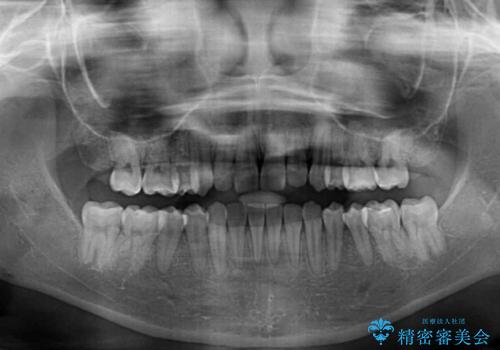

治療期間の目安は2年半~3年間でしたが、予定通り治療が進み、2年半弱で終えることができました。

歯列はきれいに整い、治療期間も予定通りであり、患者様には大変満足していただきました。